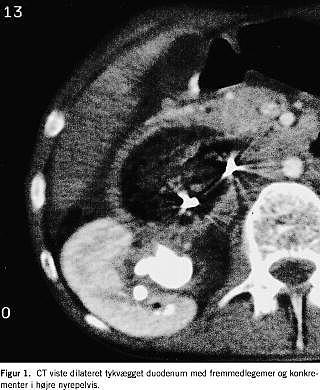

Indlæggelsen skyldtes enterokok-UVI. Patienten var febril, men alment upåvirket og med normal tarmfunktion. Biokemi: C-reaktivt protein 168 mg/l, leukocytter 13,9 × 109 ml-1 og hæmoglobin 5,0 mmol/l. Ved skanning sås der i tarmen røntgentæt materiale, som også passerede over i de højresidige urinveje i pelvisområdet (Figur 1 ). Derudover sås der luft i højre pyelogram og luft i blæren.